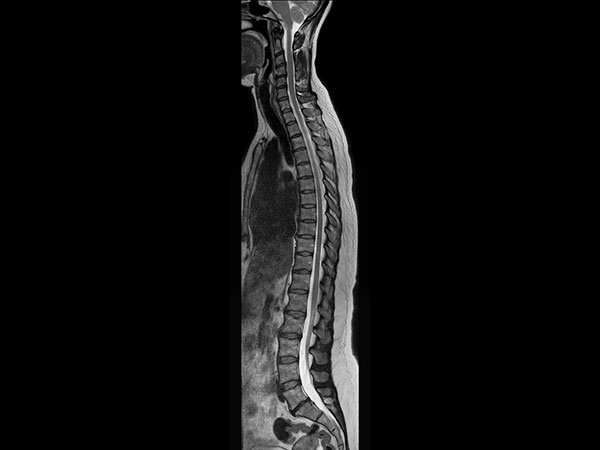

Total Spine on BlueSeal magnet